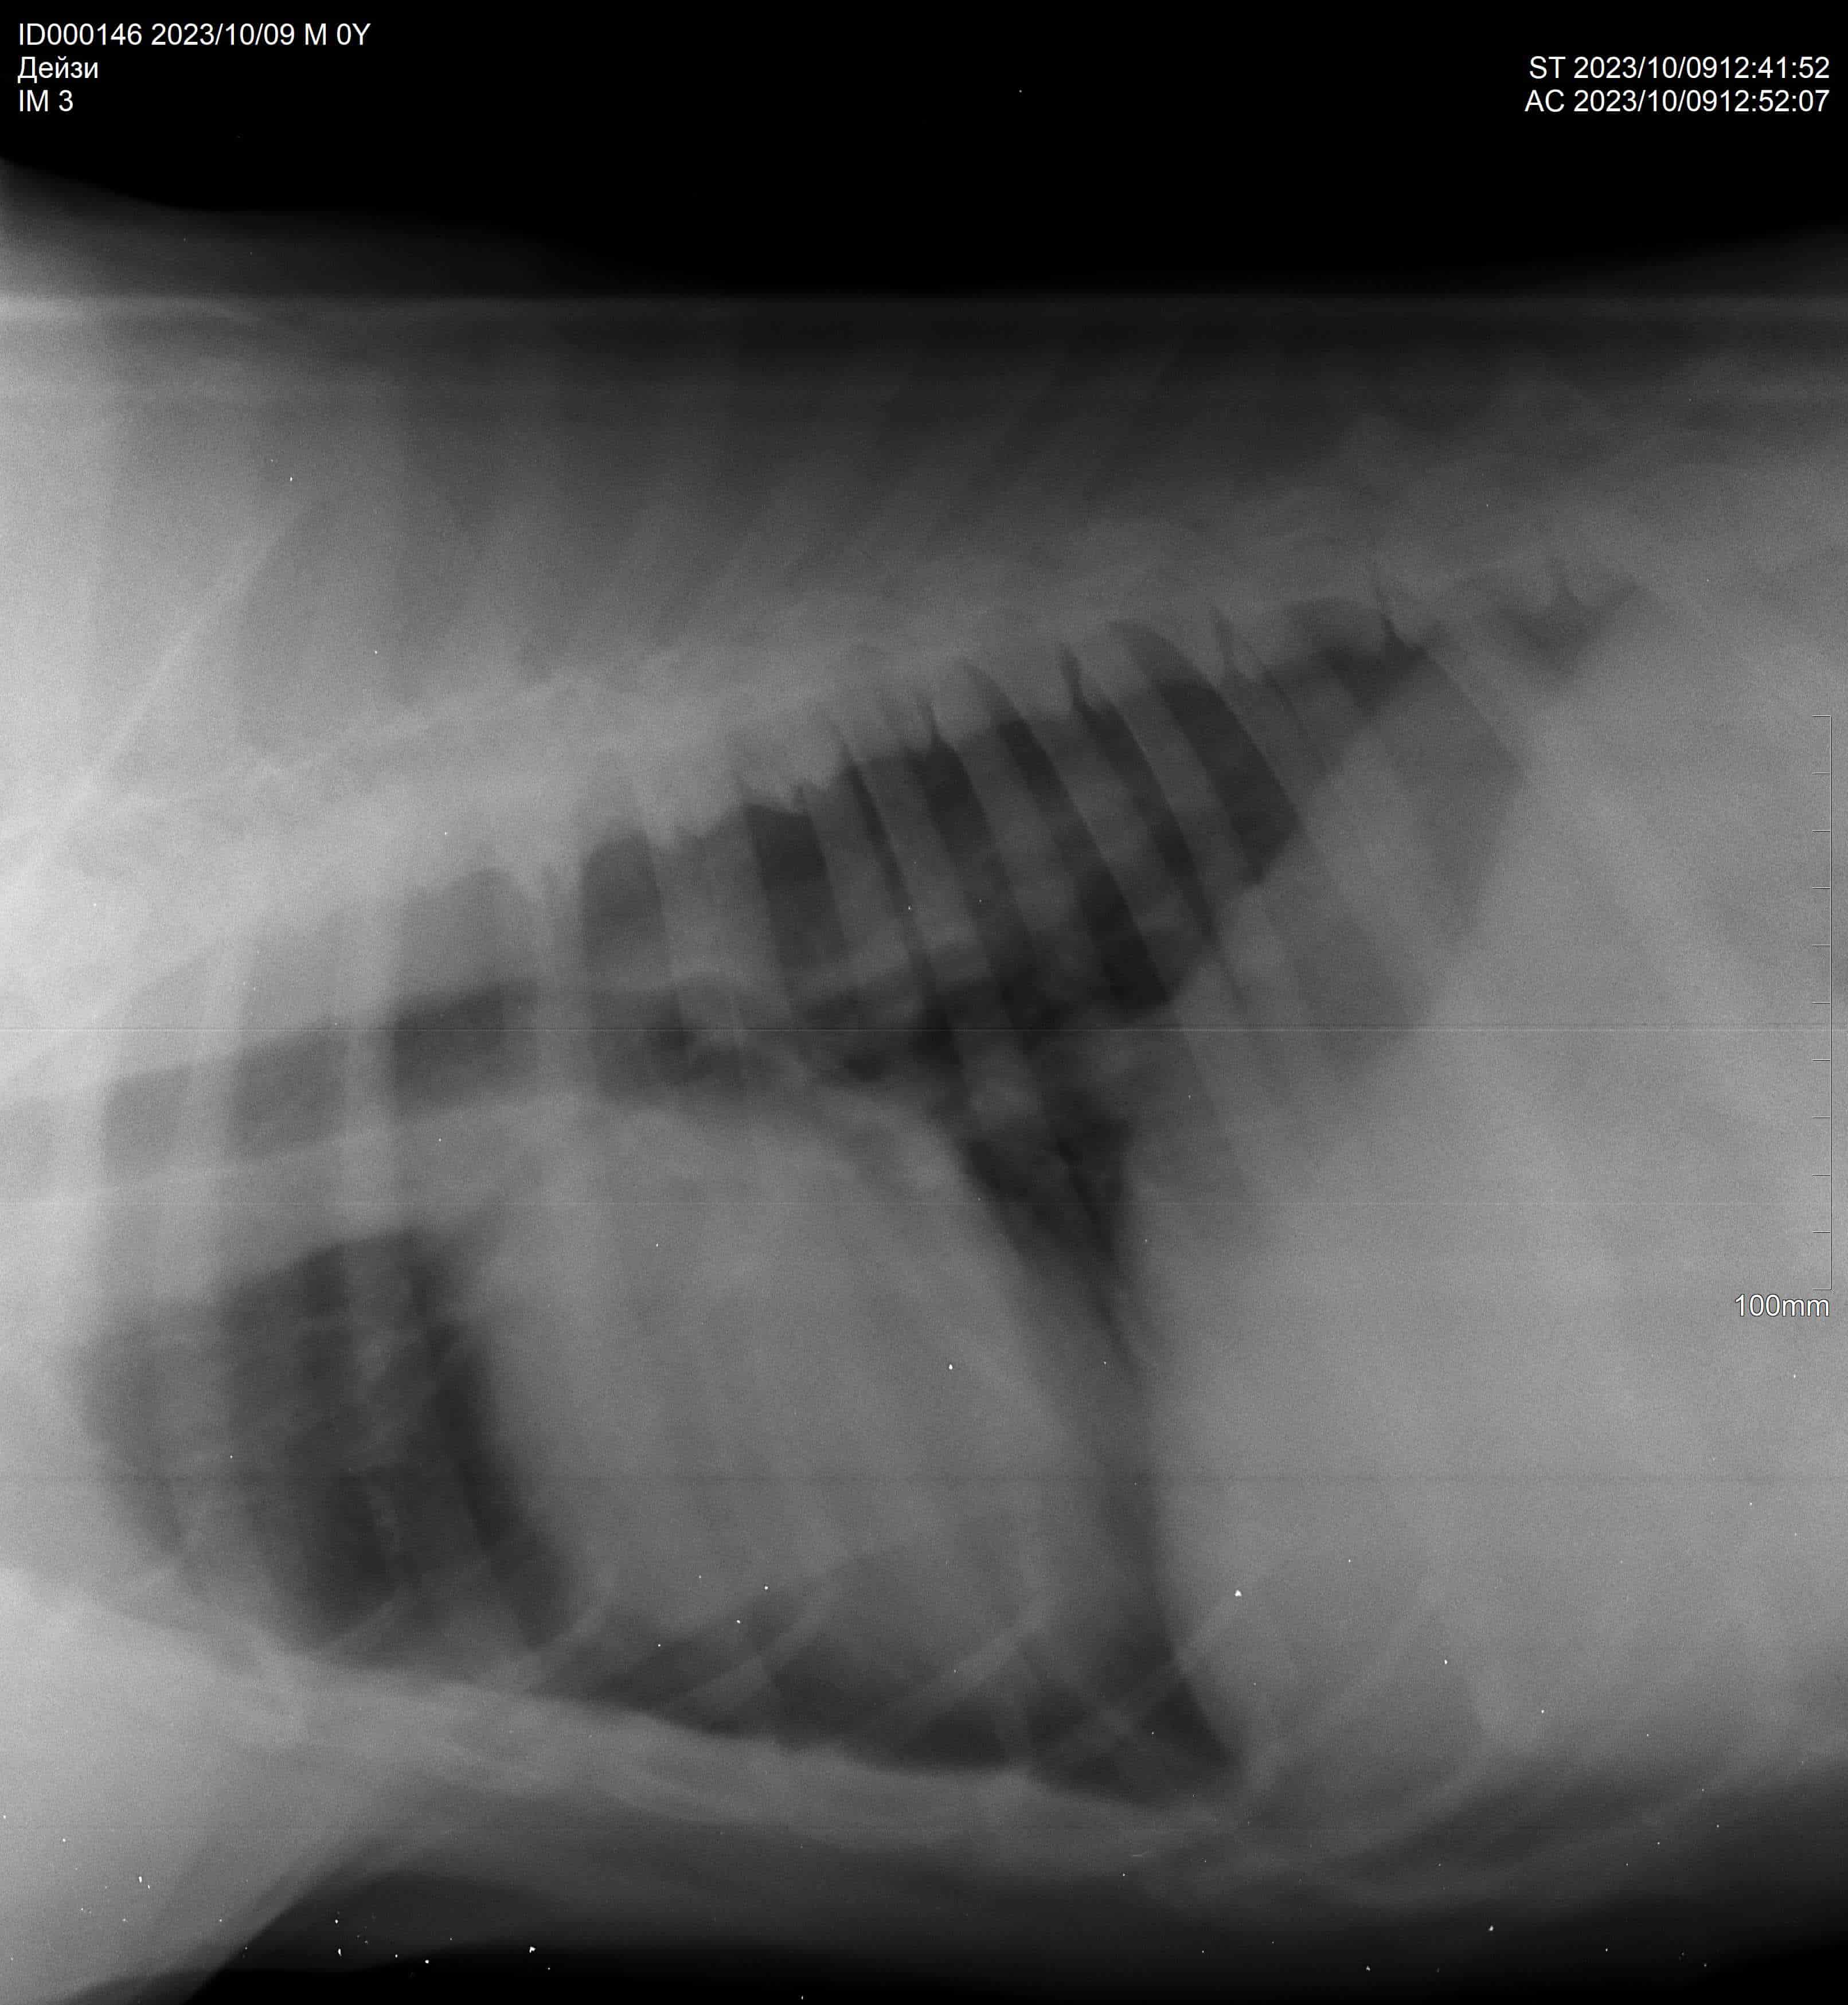

Операция и кардиография

Выписка после операции